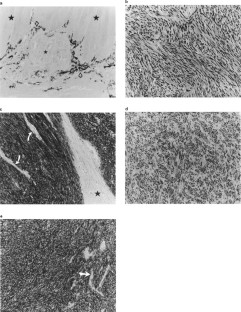

The c-kit gene encodes a transmembrane receptor kinase (KIT) which is expressed in the majority of human gastrointestinal stromal tumors (GISTs), a subtype of gastrointestinal mesenchymal neoplasms. A previous study identified mutations in the juxtamembrane (JM) domain of c-kit in five of six GISTs (Science 279: 577, 1998). To better define the frequency and spectrum of c-kit gene mutations in mesenchymal neoplasms of the GI tract that had been characterized for KIT protein expression, we examined archived tissue samples for mutations in the JM domain by PCR amplification and DNA sequencing. c-kit JM domain mutations were found in nine of 56 mesenchymal tumors (46 GISTs, eight leiomyomas, two leiomyosarcomas) and occurred exclusively in GISTs (21%). Seven of the nine mutations consisted of intragenic deletions of one to 19 codons. There was one insertion mutation that added 12 codons and one missense mutation (Val560Asp). None of the mutations disrupted the downstream reading frame of the gene. The single missense mutation (Val560Asp) is very similar to the only other missense mutation reported in GISTs (Val599Asp). Of the 46 GISTs, 43 were strongly positive for KIT protein expression and negative for diffuse expression of desmin. Neither KIT expression nor gene mutations were found in gastrointestinal leiomyomas or leiomyosarcomas. We conclude that mutation of the c-kit JM domain does not occur in gastrointestinal mesenchymal neoplasms with well developed-smooth muscle differentiation, and is restricted to GISTs. However, since these mutations are only found in a minority of GISTs, further investigation into the mechanisms of c-kit gene activation in this group of neoplasms is warranted.